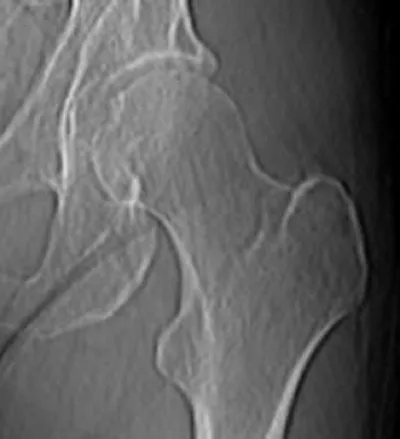

The patient came into my office in misery. He'd gone skiing and had awakened the next morning with severe stabbing pains in his back and pelvis. Another doctor had ordered a CT scan. Coming to me for a second opinion, the patient brought the scan on a disk clasped between his fingers. The radiologist's report read "degenerative disk disease, most notably at L1-L2 and L2-L3 with disk space narrowing. Air vacuum signs are seen at L1-L2, L2-L3, and L3-L4. Mild retrolisthesis of L2 on L3 is present." Yikes!

Take a look at the scan and I'll translate that for you.

The skier's X-ray

On the scan, the block-like things are the vertebral bodies and the triangular/trapezoidal shapes are the vertebral spines, those bumps that run down the middle of your own back. (These are bright white on the patient, more grayed out in the normal spine on the right.) You can see that the fourth vertebral body from the top (the second lumbar, or L-2) has slid backwards relative to the vertebral body below, which is called retrolisthesis. The space between the vertebral bodies in the middle of the image does not show the normal cushioning. The black areas are air bubbles between the vertebral bodies, caused by excessive stress pulling the vertebral bodies apart. There are also bony spurs sticking out from the tops and bottoms of the vertebral bodies in the middle of the image.